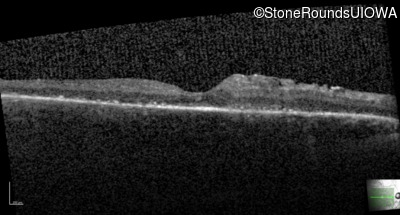

| Age at visit: 27 years |